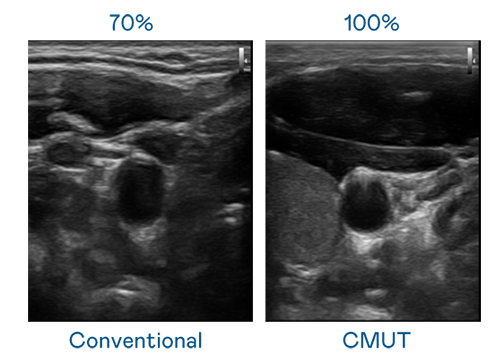

CMUT 技术是一种用电容式微机电元件来产生超音波讯号的技术。与传统 PZT 压电式技术相比,CMUT 频宽增加 30%,更宽频的超音波讯号让影像解析度大幅提升,是实现高影像品质医疗超音波扫描、促进精准医疗发展的关键技术。

大频宽带来超清晰影像

超音波影像的解析度高低,首先取决于探头能发出的讯号频宽。LEwin乐玩 CMUT 可提供高清晰的超音波讯号,提供高频宽、高灵敏度、影像纹理细节更高的超音波影像,协助医护人员缩短影像判读时间及利用精准的医疗影像进行诊断。